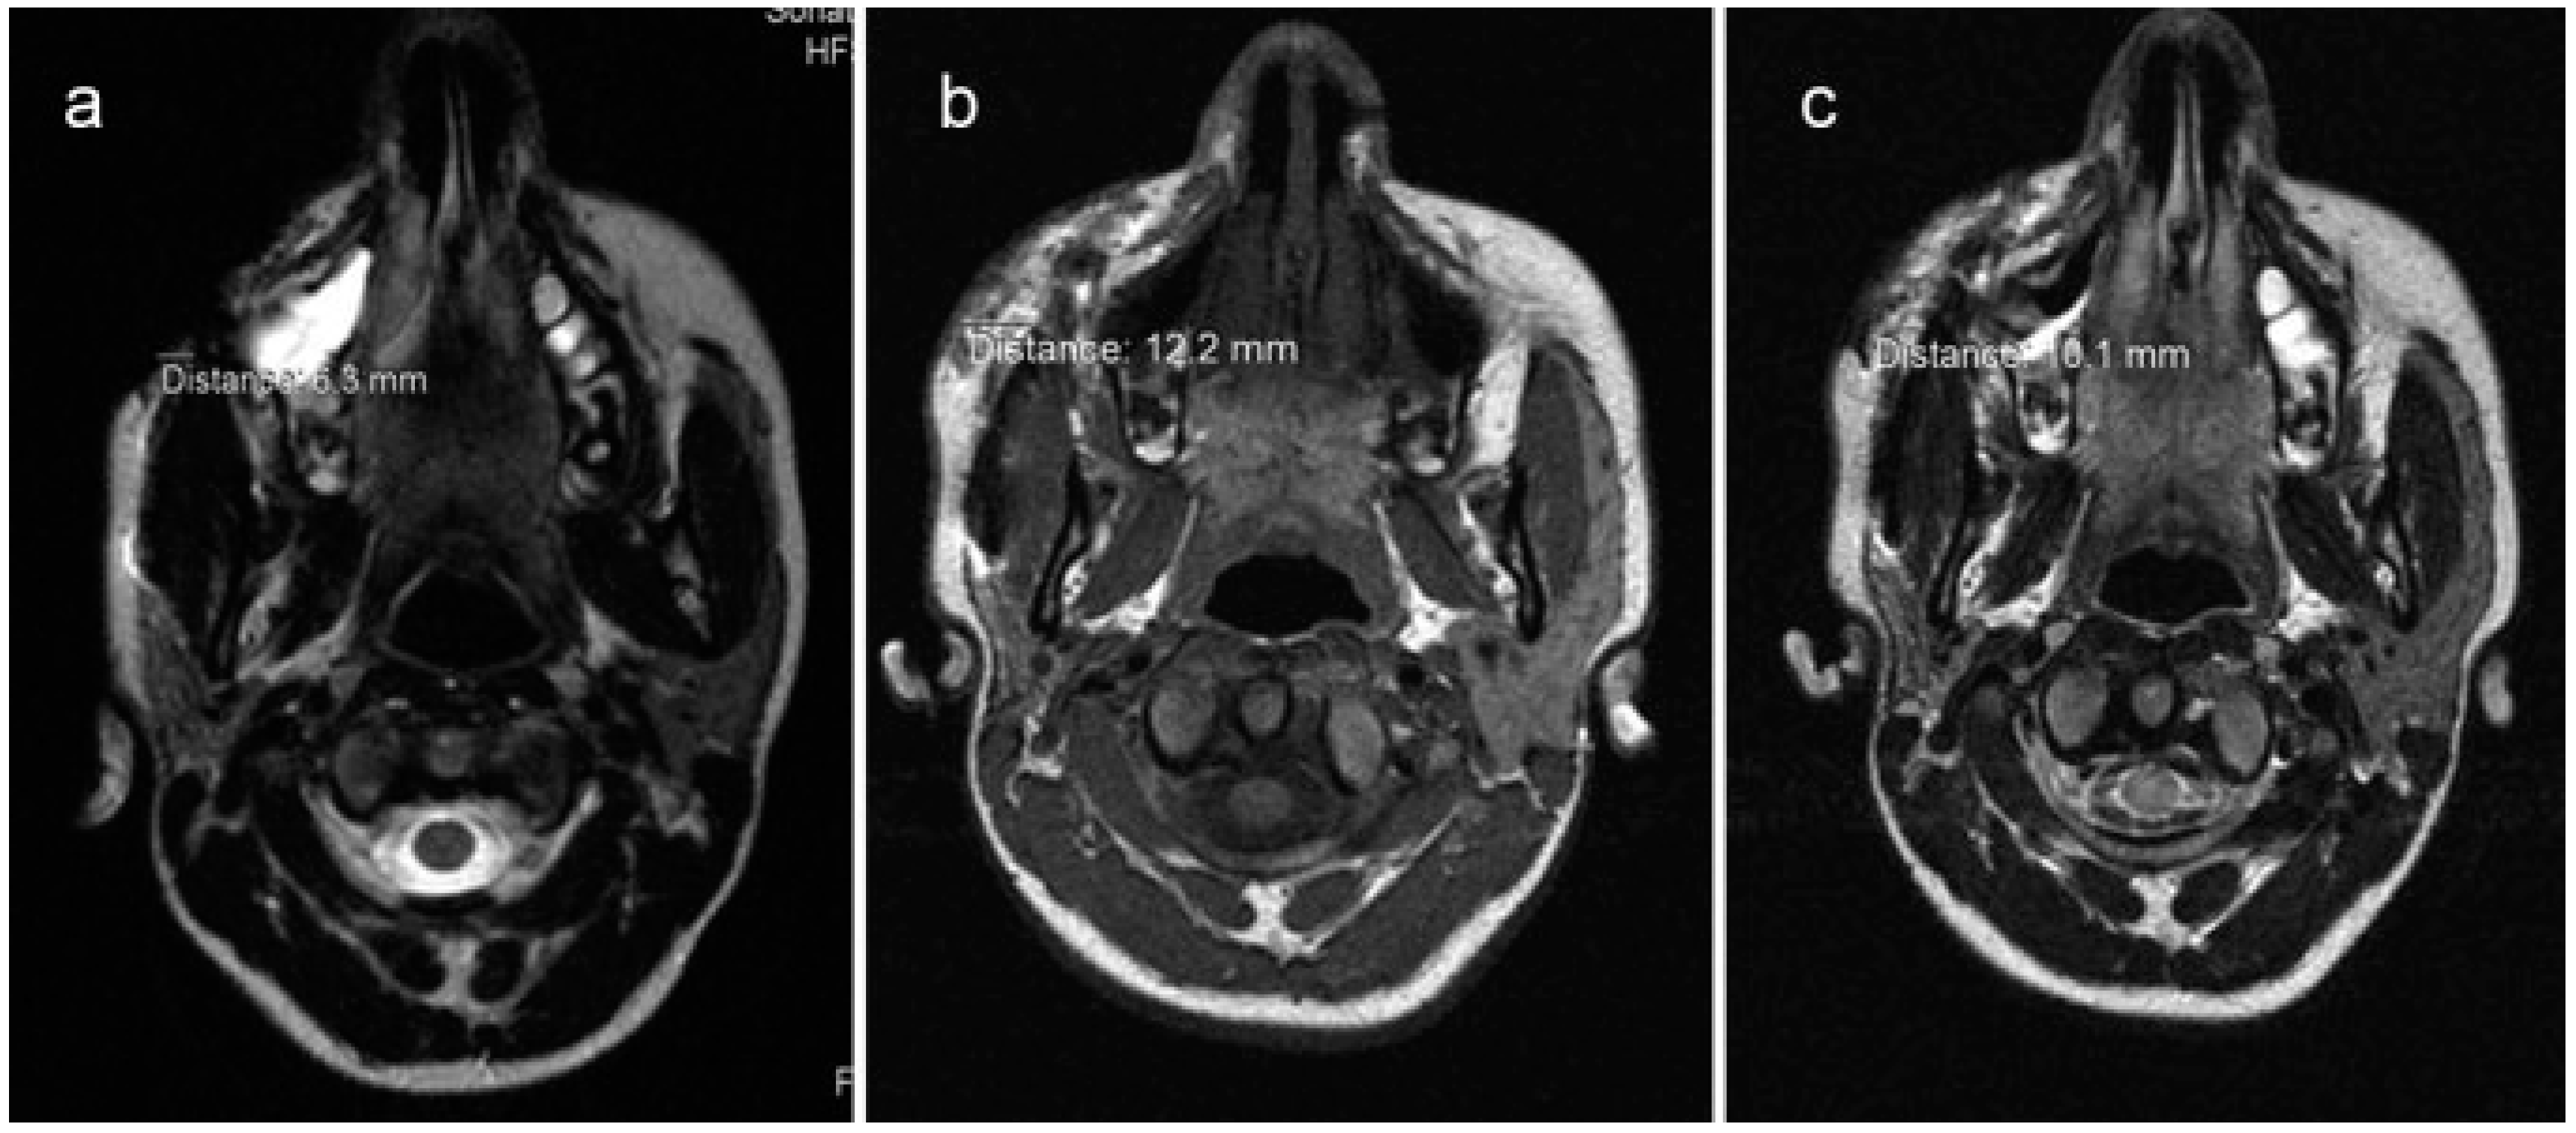

Radiographic evaluations consist of use of MRI done using a 1.5-Tesla Siemens Sonata system (Siemens Medical Solutions, Erlangen, Germany). All patients underwent MRI scans preoperatively and 1st and 12th months postoperatively. Scans were analyzed using RadiAnt DICOM Viewer 1.0.4.4439 (Medixant Ltd., Poznan, Poland). Area of fat grafting was measured in maximum dimensions in coronal, axial, and sagittal images and subsequently compared with postoperative scans (Figure 5).

Figure 5.

Example showing comparison of MRI scans in axial view. Preoperative MRI (a) depicting linear measurement of 6.3 mm. One month postoperative scan (b) shows grafted fat measuring 12.2 mm. One year postoperative scan (c) measuring 10.1 mm.